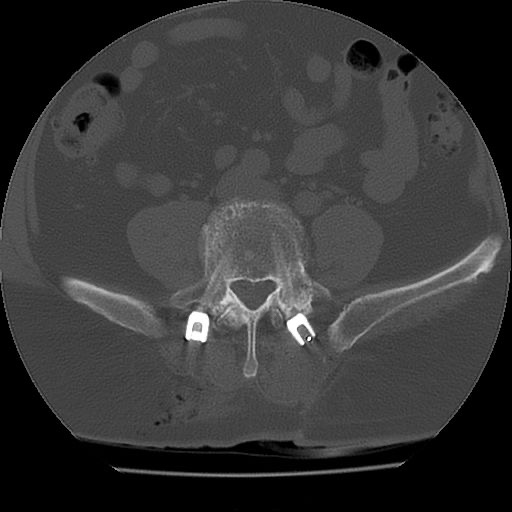

Na zdjęciach przedstawiono radiogramy pooperacyjne pacjenta, który był operowany z powodu nawrotowej dyskopatii L5-S1. Widoczna jest typowa trajektoria śrub dla techniki MIDLIF, wykorzystująca istotę zbitą kości trzonu, co dodatkowo pozwala na lepsze umocowanie implantów.

W badaniu CT kręgosłupa stwierdzono podejrzenie guza trzonu L3 ze zwężeniem kanału kręgowego.

W badaniu CT jamy brzusznej stwierdzono guza nerki prawej wykrytego de novo. Postawiono wstępne rozpoznanie rozsianego raka nerki. Są to nowotwory, które mają bogatą angiogenezę i zgodnie z zaleceniami podlegają przedoperacyjnej embolizacji nowotworu.

Implanty kompozytowe z włókna węglowego są przezierne dla promieniowania jonizującego, przez co nie generują artefaktów w badaniach pooperacyjnych, co pozwala na doskonałą jakość obrazowania i dalszej obserwacji radiologicznej (Zdjęcie 6 i 7).